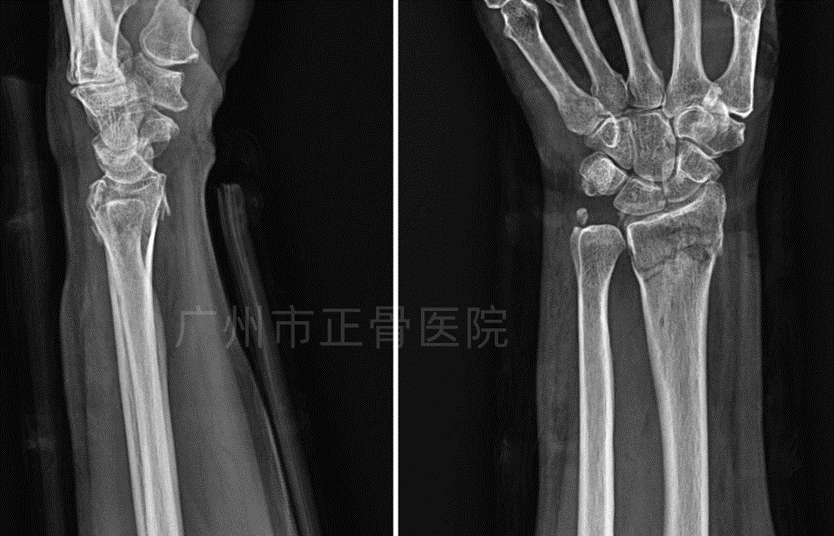

治疗:根据院桡骨远端骨折诊疗规范,运用正骨手法复位,配合小夹板外固定治疗。手法复位后复查X片示骨折对位对线良好。定期复诊,指导患者适当功能锻炼。8周后复查X线提示大量骨痂生长,骨折线模糊,予拆除夹板,指导患者功能康复锻炼。10周后腕关节活动基本恢复正常。

▲复位后,骨折端对位对线良好